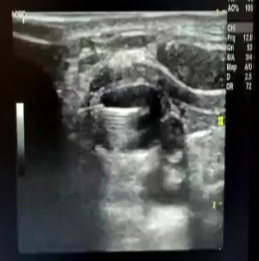

53岁男性患者因颈部前部左侧可见肿块并伴有突发性失音和轻度左上睑下垂(霍纳综合征)而就诊于急诊科。怀疑为颈部浸润性肿瘤,CT扫描显示左侧甲状腺叶有一个巨大的囊性结节,直径160 mL

经外科转到介入。超声引导抽吸(细胞学分析),随后皮质类固醇周期和言语治疗,使声音完全恢复。